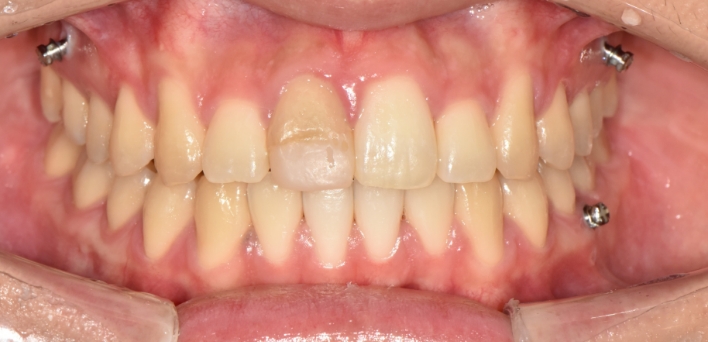

우리 얼굴에서 미소는 첫인상을 좌우합니다. 이런 좋은 인상을 위해 라미네이트를 고려 중이시라면,

많은 것들을 고려해야 합니다. 라미네이트 시 무조건 하얗고, 얇기만 한 치아가 좋은 것은 아닙니다.

개개인의 얼굴마다 비율에 맞게 이상적인 치아의 형태가 있습니다.

더서울치과의원은 정확한 안모 분석을 통한 프로파일 예측 치료로 심미성은 물론 치아 본연의 기능 회복까지 가능하도록

안면 근육과 기능, 치아 형태, 비율, 크기, 교합, 색감 등 전반적인 비율을 맞추어 본인에게 잘 맞는 치아의 형태로 복원합니다.